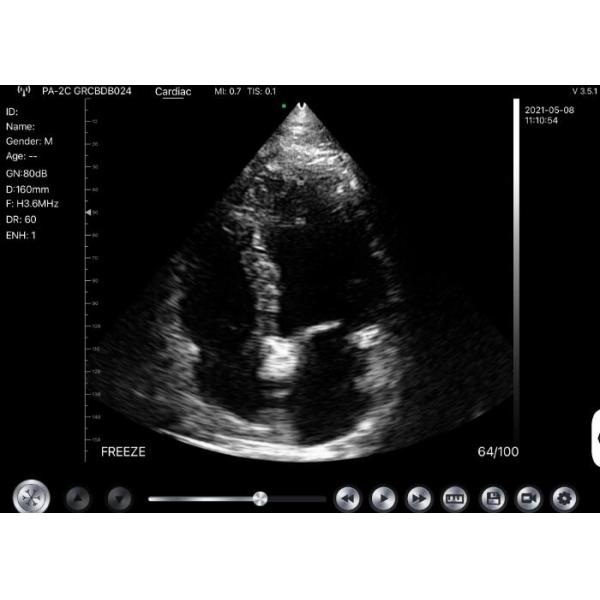

Images

|

|

Windows Pocket Ultrasound Scanner Machines Electronic Phased Array Images |